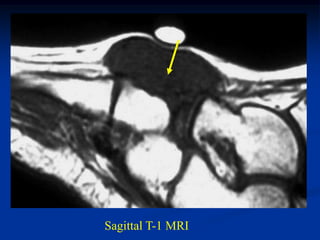

Case #261

62 year female

MFH anterior thigh

AP x-ray

Sagittal proton

density MRI

Sagittal T-2 MRI

Axial proton density MRI

Axial T-2 MRI

Case #261 62 yearfemale MFH anterior thigh AP x-ray